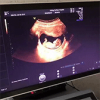

孕期产检是监测宝宝健康发育的重要手段,每一项检查 ...

女性怀孕后,都会定期的去医院进行孕期检查,因为这样 ...